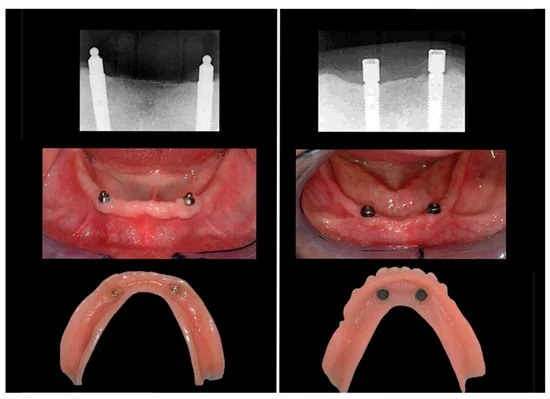

جراحی ایمپلنت دندان جراحی ایمپلنت دندان با قرار دادن ریشه دندان مصنوعی انجام می شود. این ایمپلنت ها با استخوان فک شما پیوند می خورند و به دندانپزشک یا جراح دهان و دندان اجازه می دهند